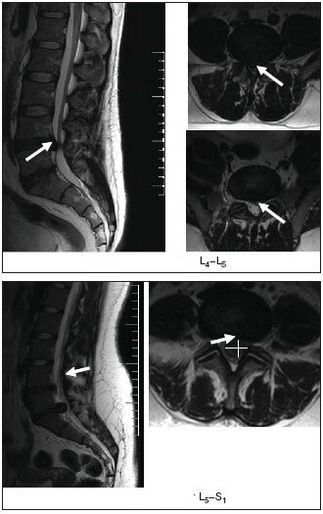

- Magnetic resonance or computed tomography will show intervertebral hernias, structural disorders of the spine, problems with surrounding tissues (nerves, muscles, blood vessels).